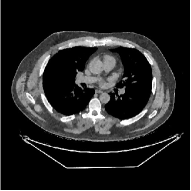

This section compares the reconstruction quality and runtime among the proposed MBIR method, PWLS-ST-, and other three MBIR methods, PWLS-EP, PWLS-DL, and PWLS-ST-. Table I shows that, for both 2D and 3D sparse-view CT reconstructions of the XCAT phantom, the proposed PWLS-ST- model outperforms PWLS-EP and PWLS-ST- in terms of RMSE. In addition, PWLS-ST- using a square transform (of size ) achieves lower RMSE than PWLS-DL using an overcomplete dictionary (of size ) for 2D sparse-view reconstructions. Fig. 3(a) and Fig. 4 show the reconstructed images for 2D and 3D phantom experiments, with different reconstruction models and different number of views. (See the corresponding error maps in the supplement.) The proposed PWLS-ST- consistently gives more accurate image reconstructions compared to other MBIR methods. Specifically, PWLS-ST- has smaller errors in the heart region (see zoom-ins in Fig. 3(a)) of 2D reconstructions than PWLS-DL and PWLS-ST-. In addition, compared to PWLS-ST-, PWLS-DL and PWLS-ST- have some ringing artifacts around the edges with high transition, e.g., edges between air and soft tissues. (See a comparison of profiles of PWLS-ST- and PWLS-ST- in the supplement.) In particular, PWLS-ST- and PWLS-DL give more visible ringing artifacts for 2D reconstruction from fewer views, and PWLS-ST- has these ringing artifacts for 3D reconstructions regardless of the number of views (see zoom-ins in Fig. 4). Table II reports runtimes of different MBIR methods in reconstructing the -views XCAT phantom scan. (FBPConvNet is a non-MBIR method and its runtime for processing a image is approximately one second with a TITAN Xp GPU.) While providing better reconstruction quality, the proposed Algorithm 1 of PWLS-ST- has shorter runtime compared to the algorithms of PWLS-DL and PWLS-ST- in Section III-A. Similar to the PWLS-EP algorithm, the reconstruction time of the PWLS-DL, PWLS-ST-, and PWLS-ST- algorithms can be further reduced by using ordered subsets [51].

![]() |

| (a) 2D fan-beam CT experiments |